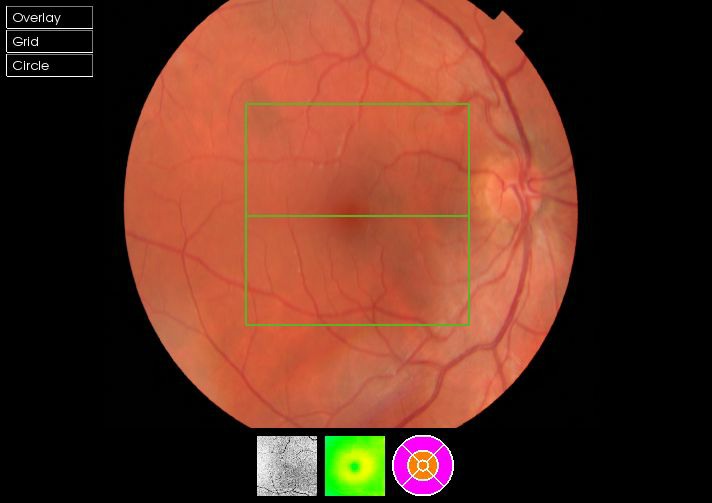

As well as the 3D scan, our instrument also takes a photograph of the eye in high resolution. This allows us to pin point any area of concern to review in depth.

A 3D section of the layers ofthe retina and vitreous jellyA 3D section of the layers of the retina and vitreous jellyAge-related Macular Degeneration Dry FormAge-related Macular Degeneration Dry FormAge-related Macular Degeneration Wet FormAge-related Macular Degeneration Wet FormThe vitreous (jelly) pulling on the retinaThe vitreous (jelly) pulling on the retinaImage of Retina (back of the eye)Image of Retina (back of the eye)